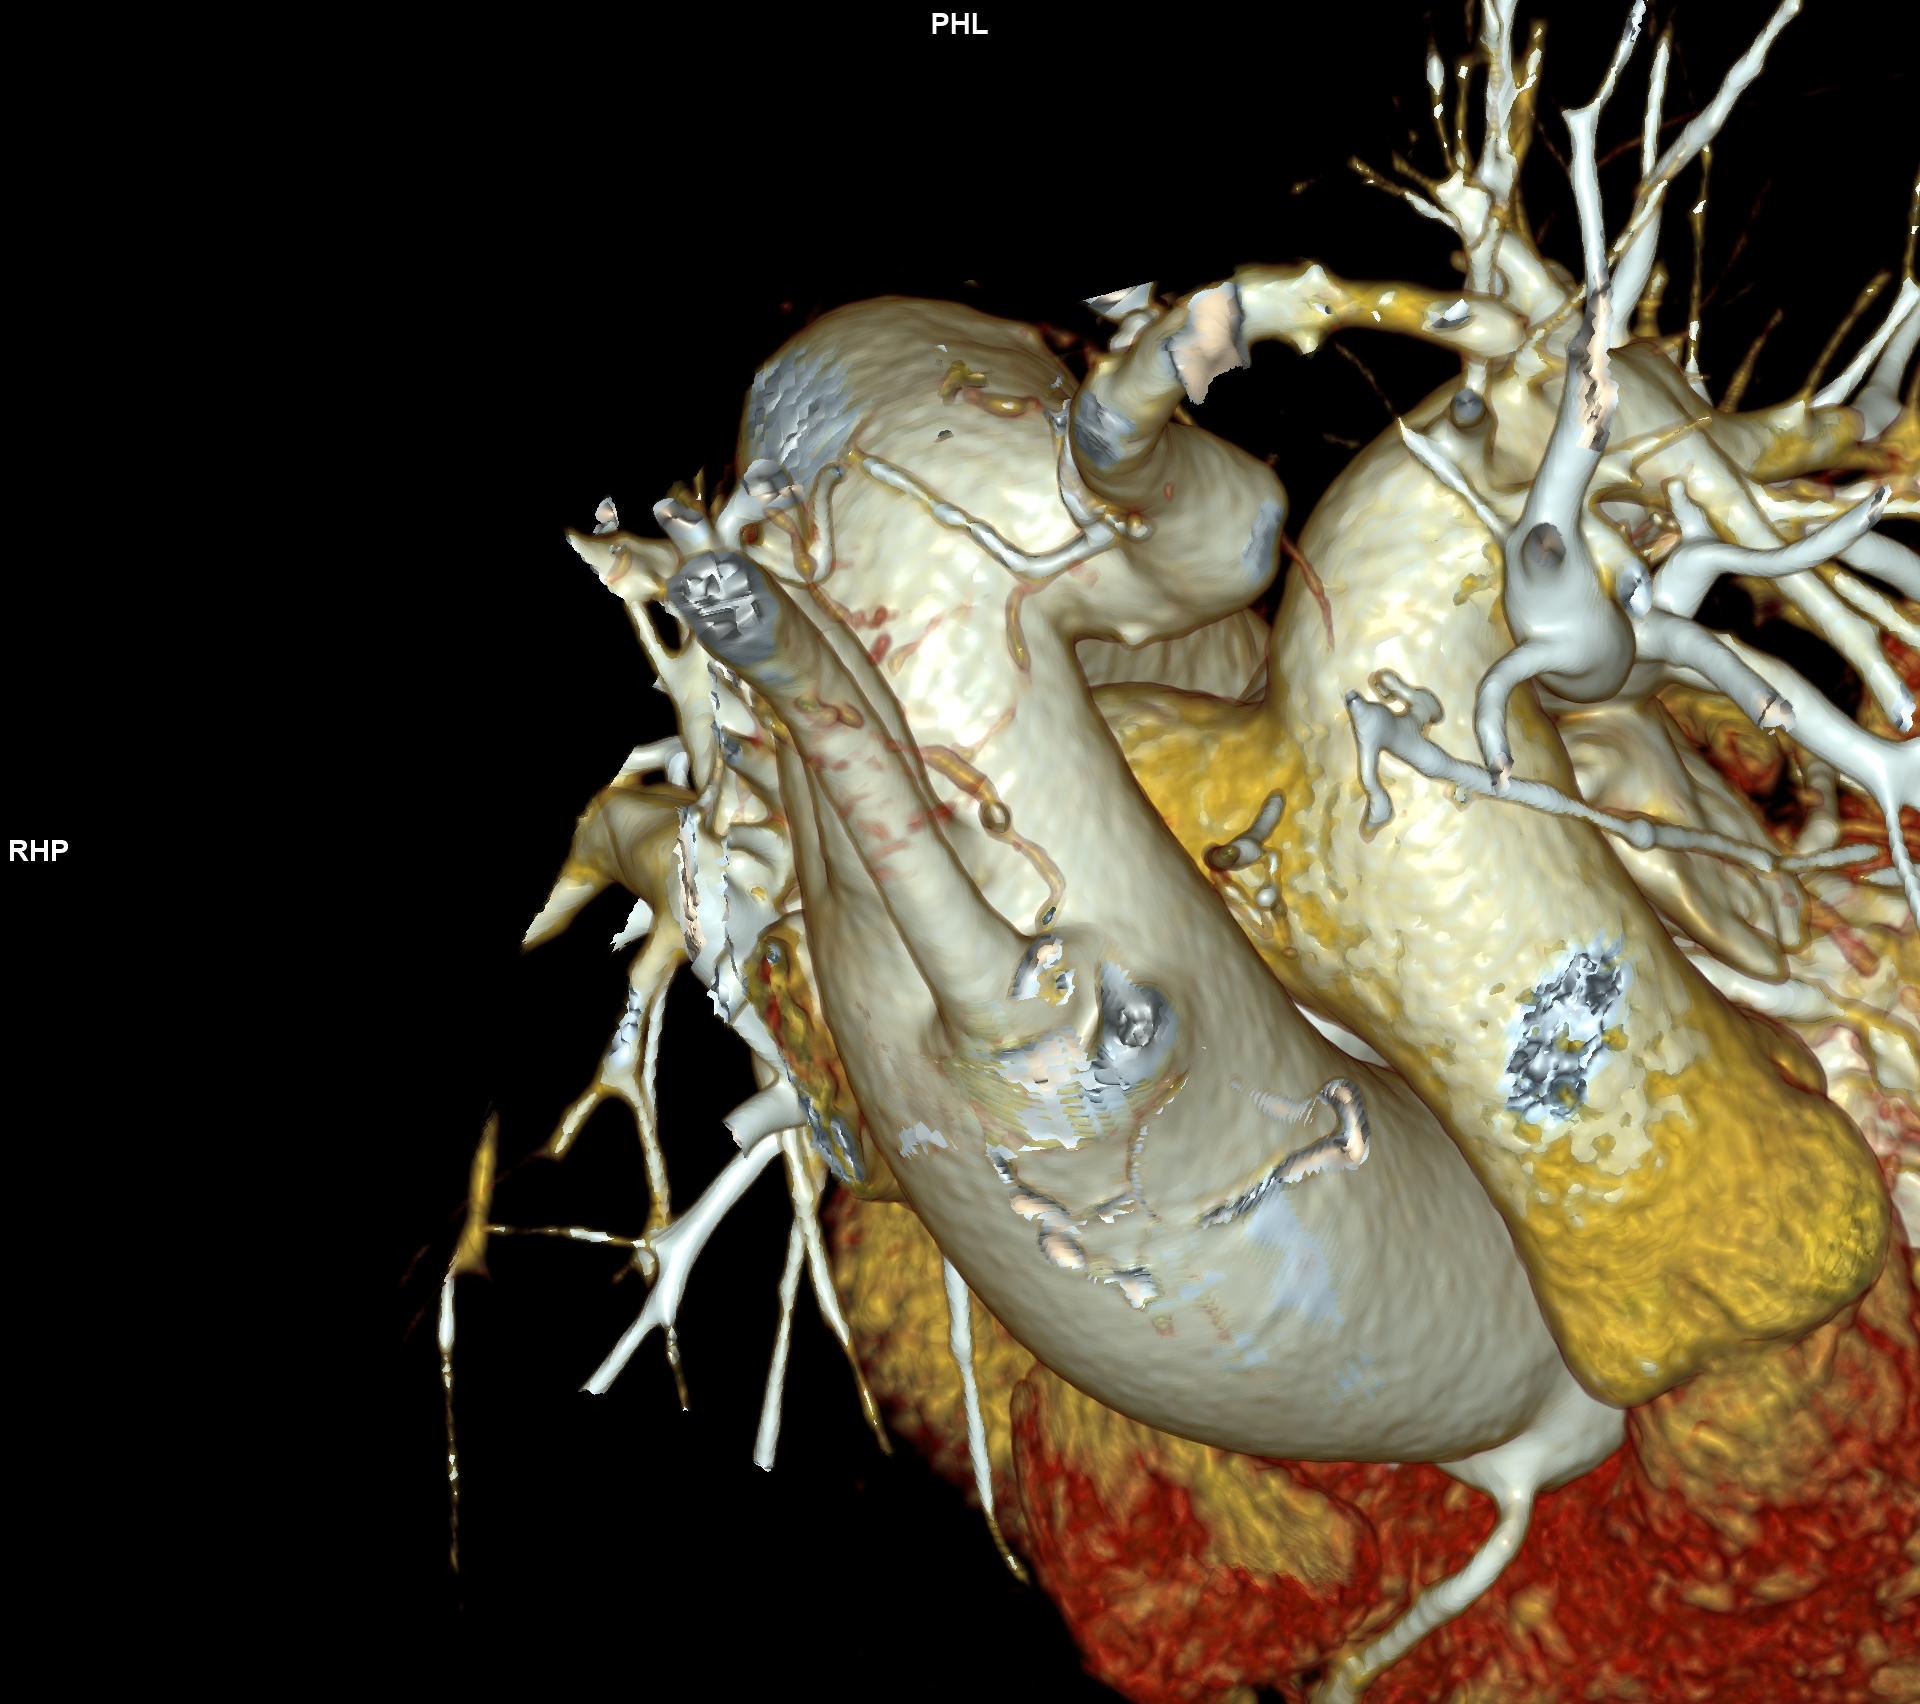

CAZ nr 57: Arc aortic de partea dreaptă si diverticul Kommerell

Figura 3, 4, 5: reconstrucție de volum 3D din achiziție angioCT toracică

Discuţie caz nr 57:  pacient asimptomatic care a efectuat angioCT de aorta toracică pentru evaluarea unei creșteri de calibru a aortei la examinarea ecocardiografica. Este o anomalie de dezvoltare a arcului aortic, ce este situat la dreapta, cu originea arterei subclavii stângi dintr-o structura diverticulară.

DE LUAT ACASĂ!!! Diverticulul Kommerell este considerat a fi o eroare de dezvoltare a celui de-al patrulea arc aortic dorsal; a fost original descris la pacienții cu arc aortic la stânga ca o structura diverticulara de origine a arterei subclavii drepte aberante ce are origine din aorta după originea arterei subclavii stângi și apoi are traseu transmediastinal ajungând în fosa subclaviculară dreaptă (denumită și arteră lusoria pentru că produce la pacienți disfagie denumită disfagia lusoria).